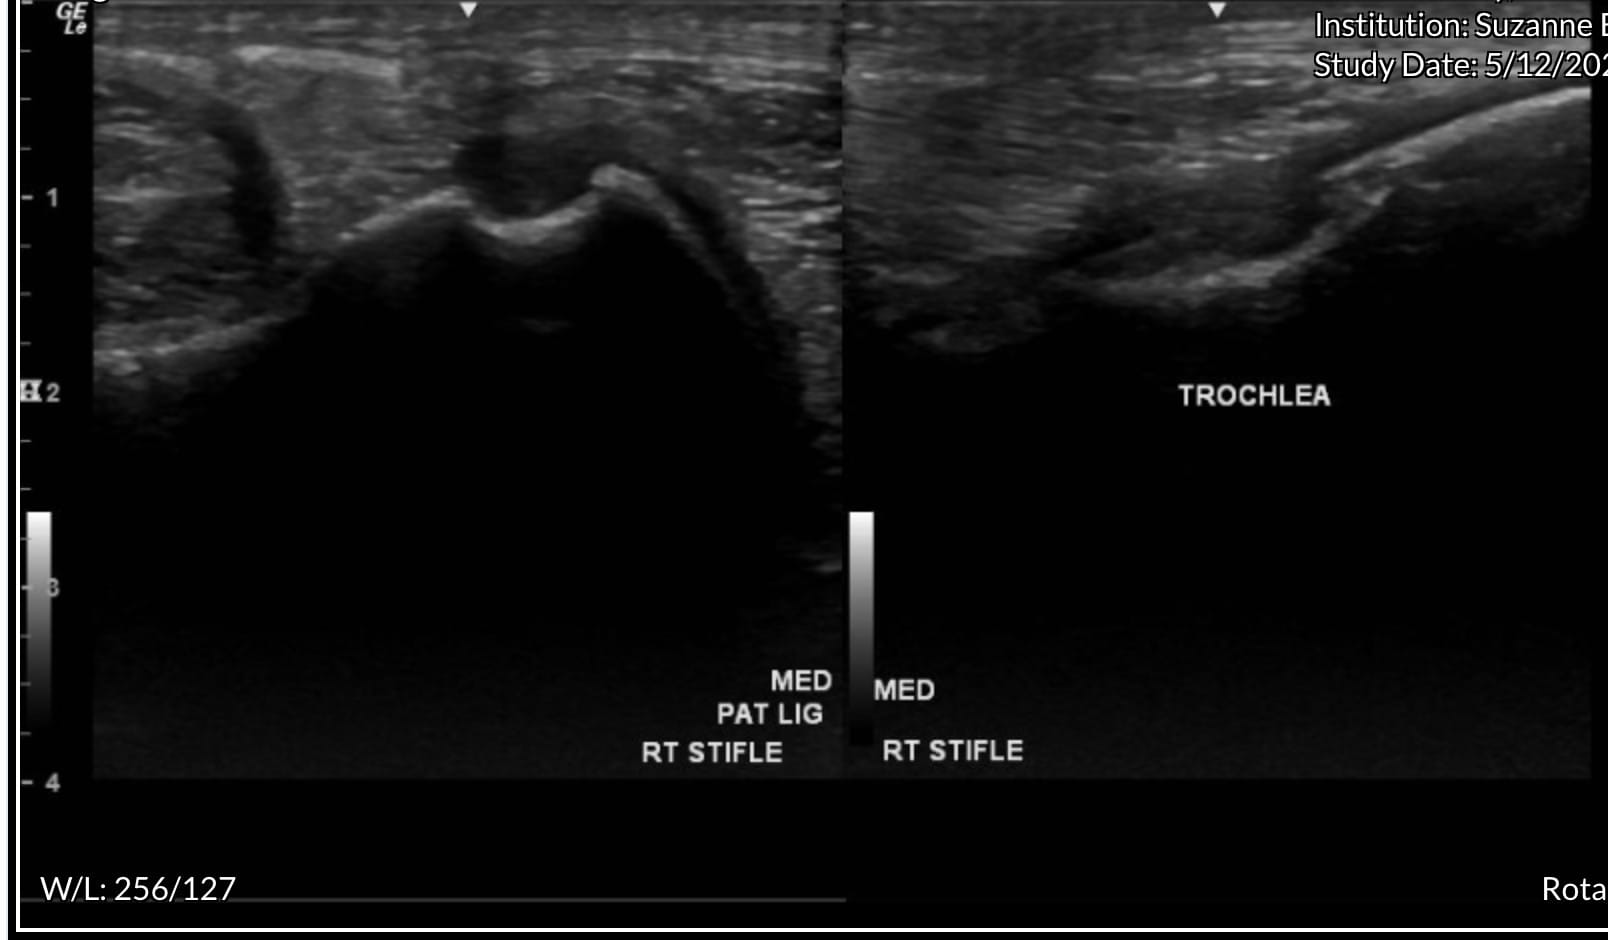

Ultrasound of the right stifle showed moderate medial femorotibial joint effusion with small hyperechoic particles, consistent with thin cartilage debris. There was a 1.5 cm x 0.5 cm defect in the abaxial portion of the medial trochlear ridge.

There was mild cranial meniscotibial ligament desmopathy. There was mild degenerative change in the axial portion of the medial meniscus. There was mild sonographic evidence of axial subchondral bone remodeling of the medial condyle at the level of the most weight-bearing portion. Ultrasound of the left stifle showed similar but less pronounced changes.